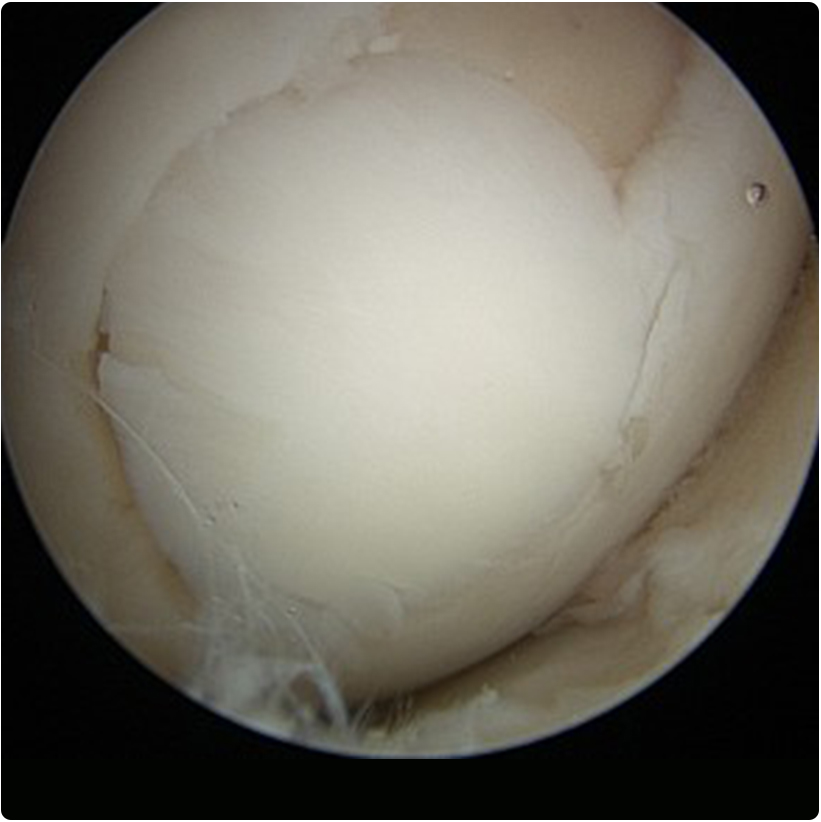

1- Artroskopik eklem debridmanı: özellikle küçük ve tam kat olmayan kıkırdak kayıplarında kapalı bir yöntemle 2-3 küçük delikten girilip kamera eşliğinde eklem içi gözlenir, kıkırdağın düzensiz ve hareketli bölümü özel traşlayıcı ve radyofrekans cihazı kullanılarak temizlenir ve daha düz bir yüzey elde edilmeye çalışılır. Bu yöntemle aynı anda eklem içindeki diğer sorunlar (örneğin menisküs  veya bağ yırtıkları) da aynı anda tedavi edilebilir.